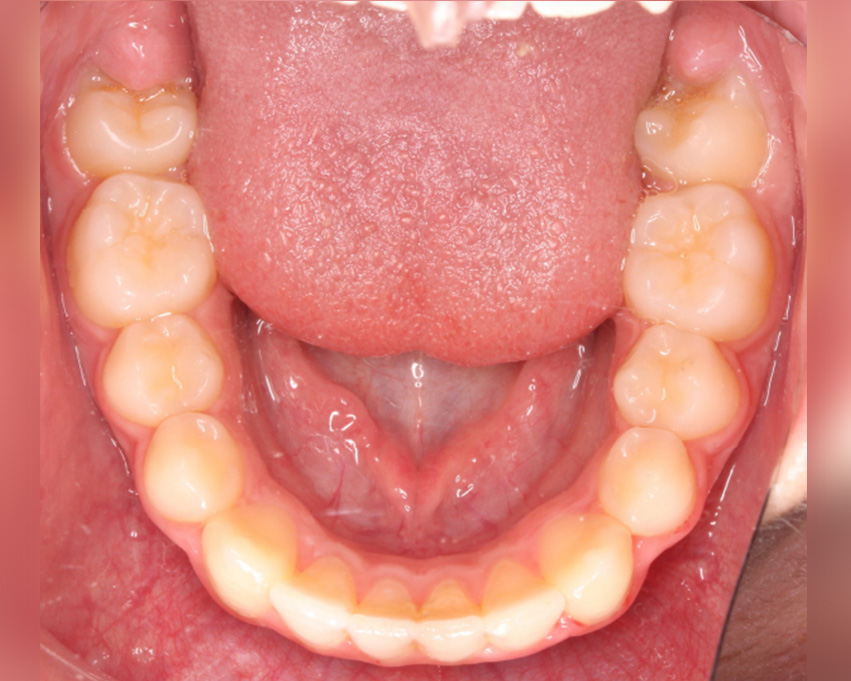

In the lower arch, anterior intrusion was planned together with proclination and in posterior teeth extrusion was applied and for that horizontal beveled attachments were placed on those teeth to extrude.